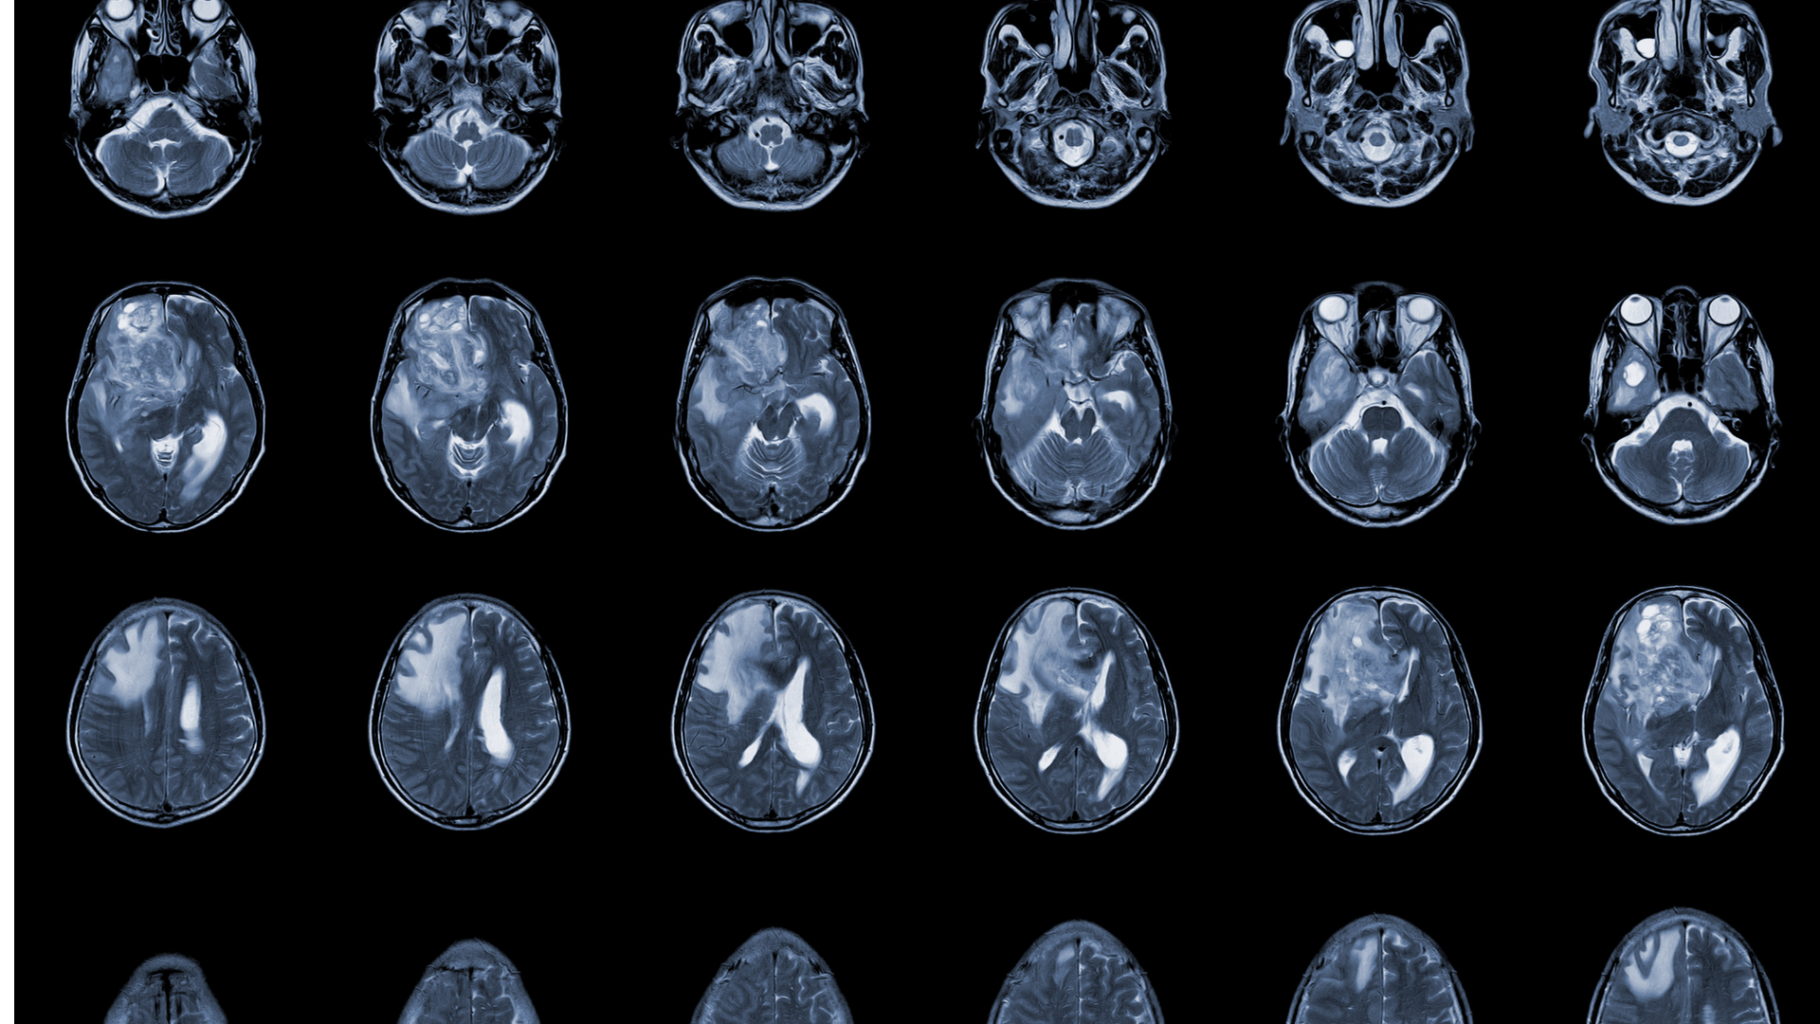

This may play an important role in the treatment of the most common and most lethal brain tumor – glioblastoma (GBM) where despite EBRT treatment nearly 100% of patients will experience a local recurrence. The use of relevant cellular models to investigate the biological effects of ionizing radiation is of crucial importance, namely the molecular and cellular mechanisms involved in the radiation response in GBM.

Until now most of targeted radionuclide therapy pre-clinical radiobiological studies have been performed in conventional in vitro cell culture systems, which fail to recapitulate some of the features of in vivo tumors. Multicellular tumor spheroids are 3D culture models that can better replicate the metabolic and proliferative gradients of in vivo tumors, and are expected to better contribute to estimate the clinical potential of pharmaceuticals, particularly in a complex environment such as the brain.

The project envisages a strategy for the evaluation of a radiotheranostic approach to GBM based on the use of advanced 3D models. First we will use 3D spheroids, developed in the MD Anderson Cancer Center, and at a later stage explore cerebral organoids that will simulate the microenvironment of a human brain and GBM tumors, allowing a more realistic evaluation of the theranostic potential of 64CuCl2.